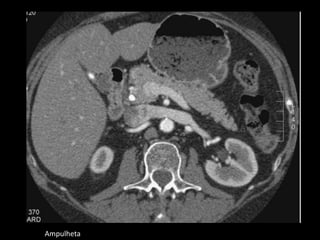

Ampulheta

TCMD: contorno lobulado